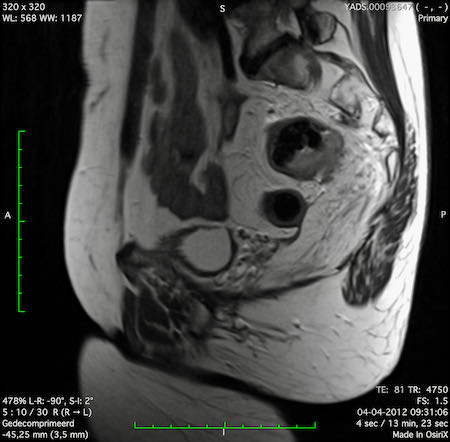

Hình ảnh

Các hình ảnh được cung cấp cho thấy ung thư biểu mô tế bào nhẫn với tình trạng dày lan tỏa thành trực tràng, hình ảnh bia bắn điển hình, và sự xâm lấn mỡ mạc treo trực tràng.